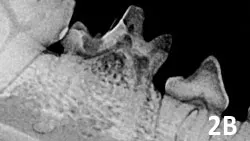

Type 2: There is loss of periodontal ligament space and lamina dura from fusion of tooth root and alveolar bone (ie, dentoalveolar ankylosis). The resorbing tooth structure may appear less radiopaque than the unaffected tooth (ie, replacement resorption). If the lesion extends into the oral cavity (See Figure 2B), using a high-speed water-cooled handpiece the crown can be reduced in height below the gingiva before closure.

A radiographic image showing the dental structure of a canine jaw, highlighting the roots of the teeth and surrounding bone. The image provides detailed visualization of potential dental pathology, such as periodontal disease or root resorption.

Figure 2B

Type 2 resorption in the deciduous mandibular fourth premolar with exposure to oral cavity; extraction is indicated.